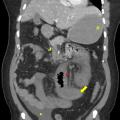

Les atteintes possibles des petits vaisseaux du foie sont au nombre de quatre (fig. 1)  :la maladie vasculaire porto-sinusoïdale (MVPS)  ;le syndrome d’obstruction des sinusoïdes, appelé également «  maladie veino-occlusive  », caractérisé par l’obstruction des sinusoïdes et des veinules hépatiques par des…

Thrombose porte et ischémie mésentérique veineuses

La thrombose de la veine porte (TVP) se caractérise par l’obstruction, le plus souvent par un thrombus, de la veine porte et/ou de ses branches portales (droite et/ou gauche). Cette obstruction peut être partielle ou complète, récente (moins de six mois) ou chronique (plus de six mois) et peut également affecter les vaisseaux…